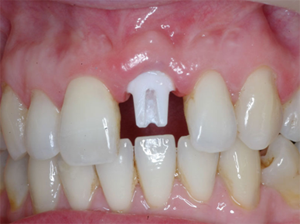

Second surgery and placement of healing collar and/or temporary crown

Second surgery is scheduled after the x rays show good bone around the implant. An incision is made to expose the heads of the implants. A collar, called a healing abutment, is placed on the head of the implant after it is exposed. This encourages the gums to shape around the neck of tooth. The collar will be in place for 10 to 14 days.

After the stitches and collar are removed, final impressions are made. These impressions will be used to make models that will look exactly like your mouth. A dental technician will use these models to make the temporary and final crowns.

An abutment and temporary crown are placed on the implant. The abutment is screwed onto the implant and tightened. The temporary crown will be in place for four to six weeks. The gums will heal around it and will look like the gums around your natural teeth. The temporary crown is made of softer material than the permanent crown. The softer material helps to cushion and protect the implant from the pressure of chewing, and gives the jawbone the opportunity to gradually get stronger.

While you are wearing your temporary crown, the permanent crown will be made. The crown is either cemented or screwed to the abutment.